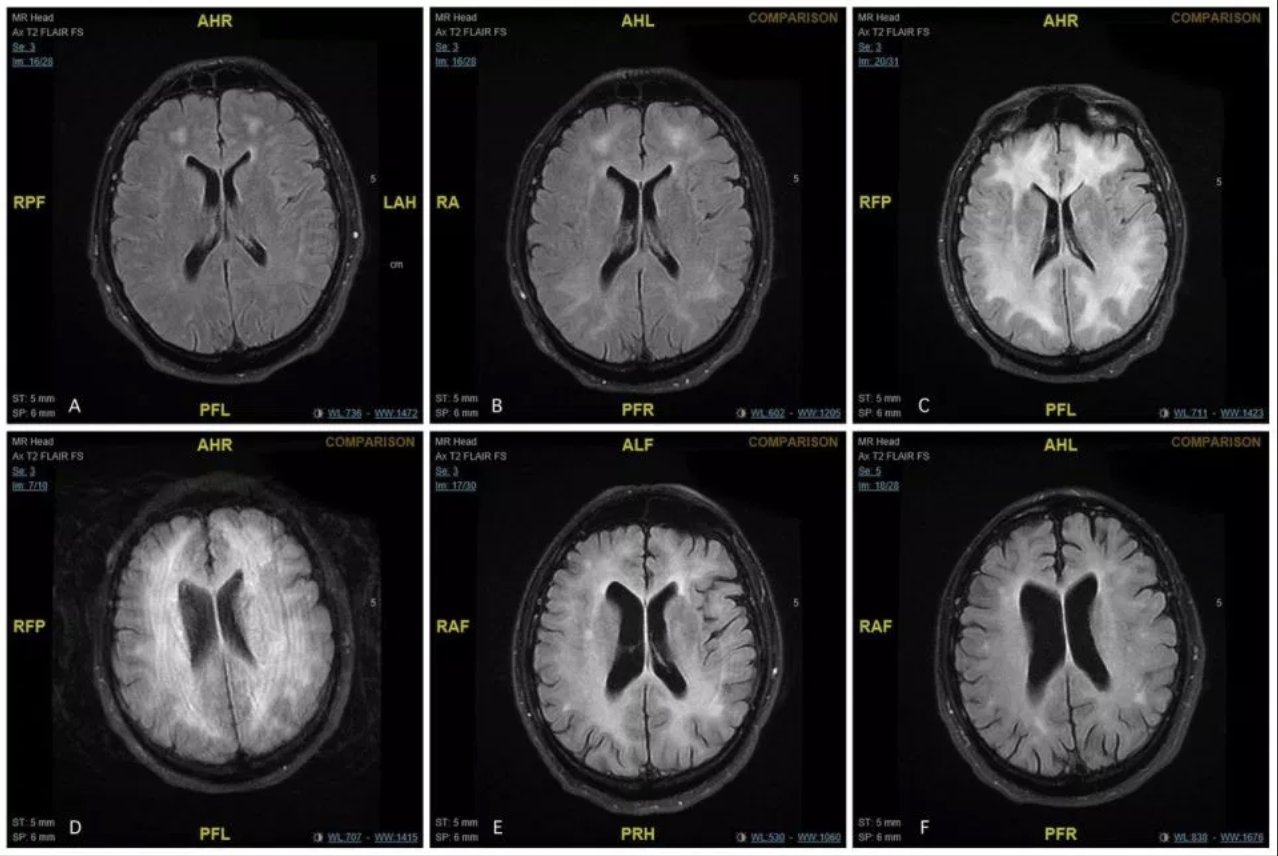

Al realizarle una tomografía, los médicos se dieron cuenta de que padecía leucoencefalopatía tóxica inducida por cocaína.

“Mientras el sujeto permanecía inconsciente, se realizaban exploraciones regulares de su cerebro y mostraban que las células nerviosas de la sustancia blanca habían muerto. La materia blanca controla el aprendizaje, la resolución de problemas, la marcha, el equilibrio y el estado de ánimo”, apuntó el estudio médico.